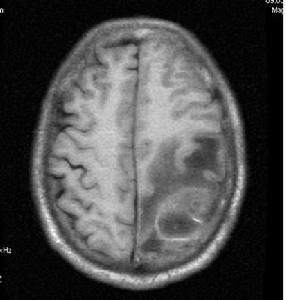

8、腦CT 是目前診斷腦膿腫的主要方法,適用於各種部位的腦膿腫。由於腦CT檢查方便、有效,可準確顯示膿腫的大小、部位和數目,故已成為診斷腦膿腫的首選和重要方法。腦膿腫的典型CT表現為:邊界清楚或不楚的低密度灶(0~15HU),靜脈注射造影劑後,膿腫周邊呈均勻環狀高密度增強(30~70HU),膿腫中央密度始終不變,膿腫附近腦組織可有低密度水腫帶,腦室系統可受壓、推移等。如膿腫接近腦室,可引起腦室管膜增強征。少數腦膿腫的增強環不均勻,或有結節狀。可是腦CT顯示的"環征"並非腦膿腫特也可見於神經膠質母細胞瘤、轉移癌,囊性膠質細胞瘤,腦梗塞和腦內血腫等。因此應結合病史注意鑑別。一般腦膿腫有感染史,CT顯示的環較均勻,伴有室管膜增強,還是容易識別。在腦炎晚期,CT也可顯示"環征",此乃因腦炎引起血腦屏障改變,血管周圍炎性細胞浸潤和新生血管形成等所致,因此腦炎的"環征"與膿腫包膜的"環征"在本質上不同。兩者的區分,除結合發病時間外,可採用延遲CT檢查法,即在靜脈注射造影劑30分鐘後掃描,腦炎原來低密度中央區也變成高密度,但膿腫中央區密度不變。由於類固醇激素有抑制炎症反應和成纖維增生、新生血管形成的作用,從而影響膿腫包膜形成,因此,對可疑病人應停用激素後重複CT檢查。

9、磁共振成像(MRI)是近年套用於臨床的新檢查方法。在腦炎期病灶呈邊緣不清的高信號改變,中心壞死區為低信號改變,T2(橫弛豫時間)延長,周邊腦水腫也呈高信號變化,灰白質對比度消失,T1(縱弛豫時間)和T2也延長。腦炎晚期的病灶中央低信號區擴大,IR(反向復原)成像示中央區仍為低強度。包膜形成期的中央區低信號,T1延長,但在長TR(重複時間)成象時原低信號變成較腦脊液高的高信號。包膜則為邊界清楚的高信號環。鄰近腦灰白質對比度恢復正常,但T1,T2仍輕度延長。因此MRI顯示早期腦壞死和水腫比CT敏感,區分膿液與水腫能力比CT強,但在確定包膜形成,區分炎症與水腫不及CT敏感。

5、電子計算機斷層腦掃描(CT)及磁共振成像檢查(MRI):自從CT及MRI用於臨床,對顱內疾患,尤其占位病變的診斷有了重大突破。CT可顯示腦膿腫周圍高密度環形帶和中心部的低密度改變。MRI對膿腫部位、大小、形態顯示的圖像信號更準確。由於MRI不受骨偽影的影響,對幕下病變檢查的準確率優於CT。CT和MRI能精確地顯示多發性和多房性腦膿腫及膿腫周圍組織情況。